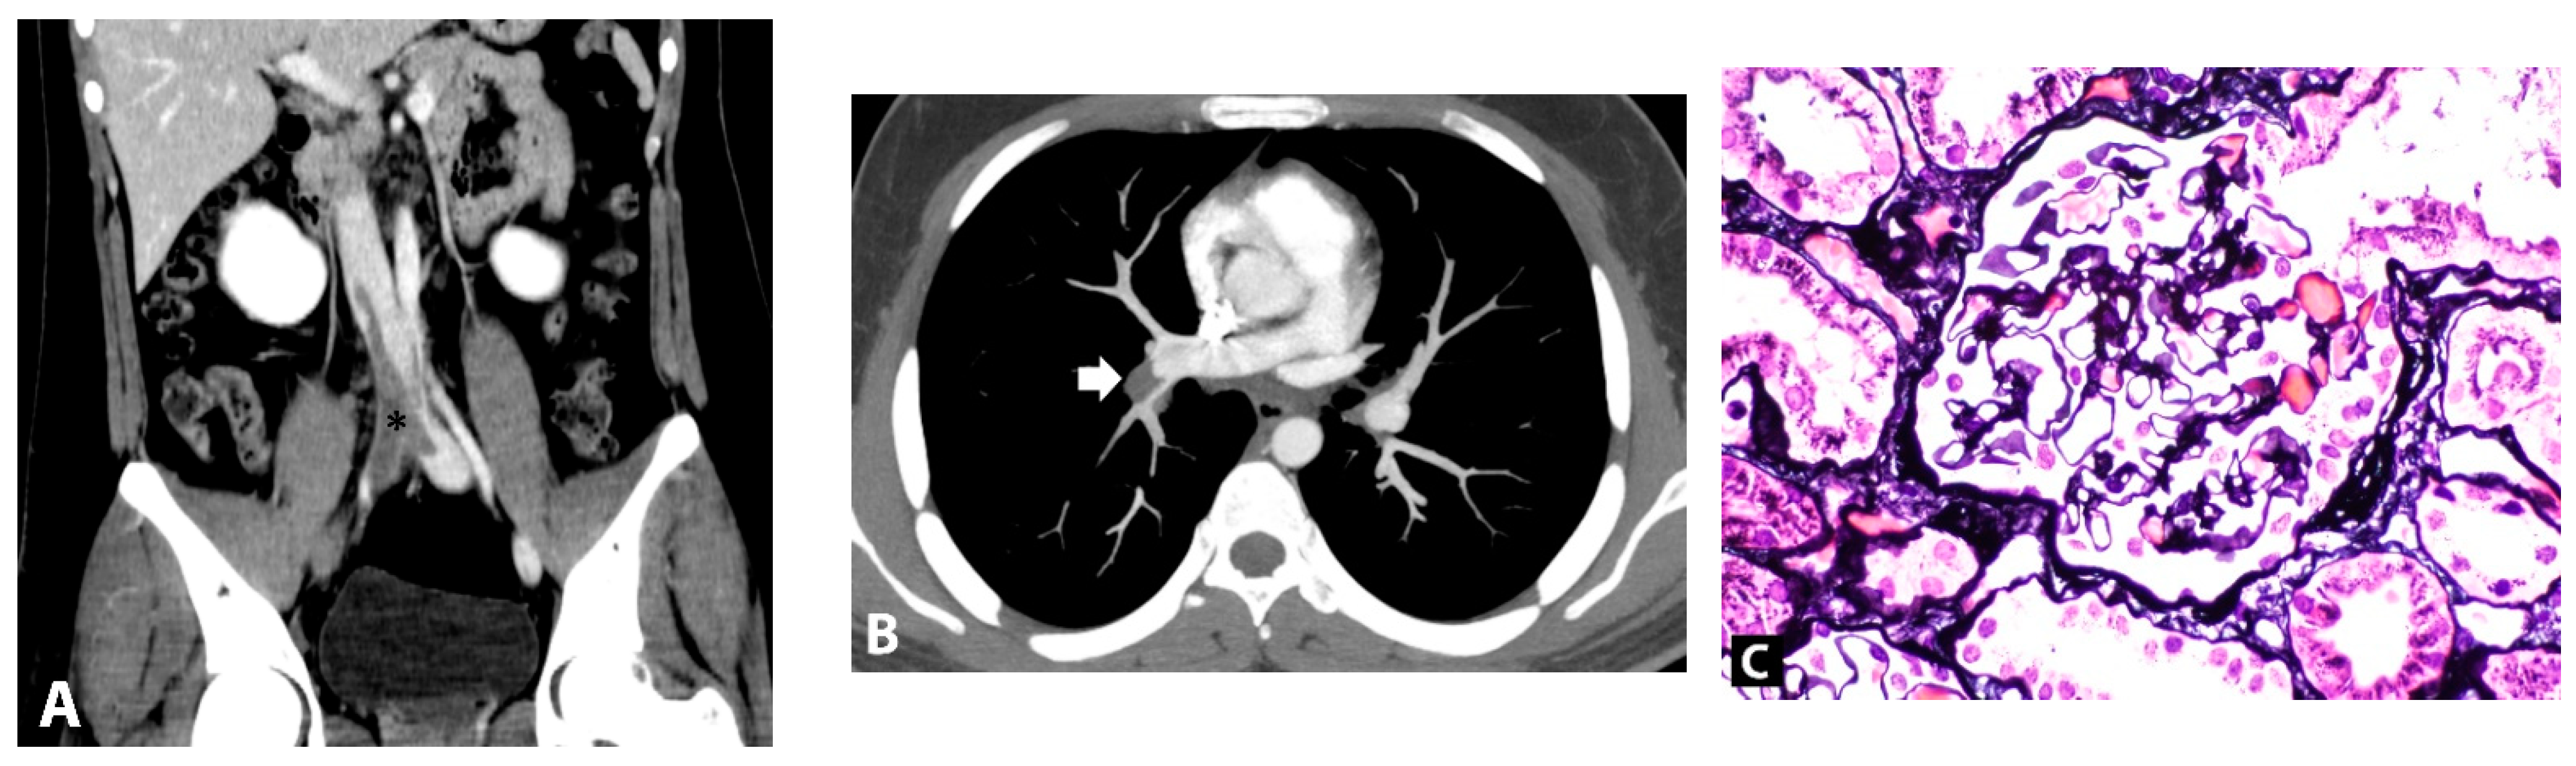

Multiple Venous and Pulmonary Artery Thrombosis as the Presenting Features of Spontaneously Reversible Nephrotic Syndrome after Exposure to SARS-CoV-2 Virus (Pfizer/BioNTech BNT162b2) Vaccination

2. Case Presentation